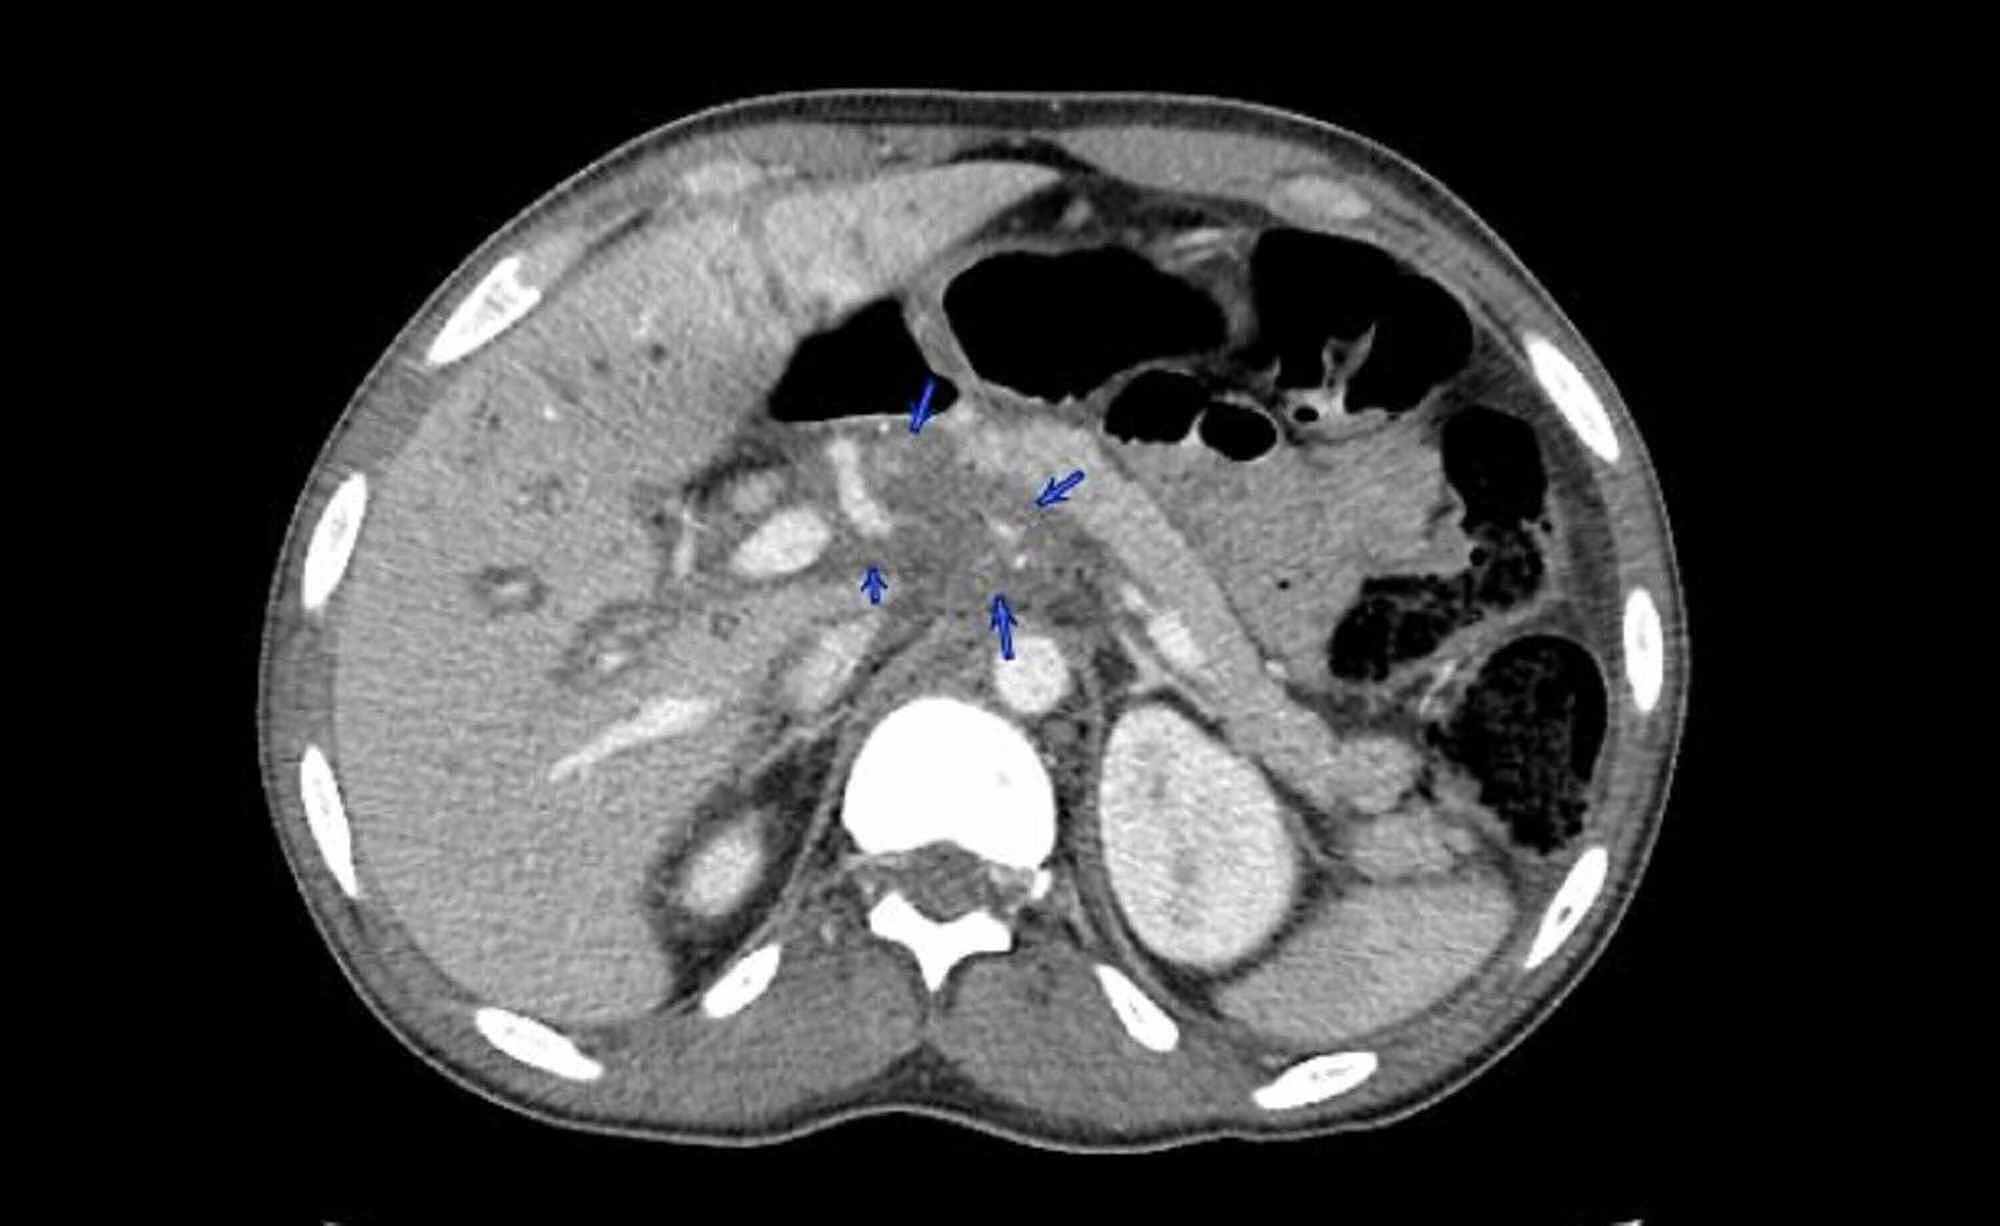

Cholestasis Cirrhosis. cholestatic liver disease is a disease that causes liver damage and. The differential diagnosis of cholestatic liver diseases is broad, and the etiologies of cholestasis vary in the anatomical location of the defect and acuity of presentation. cholestasis is defined as stagnation, or at least a marked reduction, in bile secretion and flow. cholestasis is the slowing or stalling of bile flow through your biliary system. with prolonged cholestasis, fat soluble vitamin deficiencies, fibrosis, cirrhosis, and, on occasion, carcinoma of the biliary tract or liver can occur. Cholestasis may occur in a. easl clinical practice guidelines (cpg) on the management of cholestatic liver diseases define the use of diagnostic, therapeutic and preventive modalities,. It can be a problem in your liver or in your bile ducts. cholestasis describes impairment in bile formation or flow which can manifest clinically with fatigue, pruritus, and jaundice.